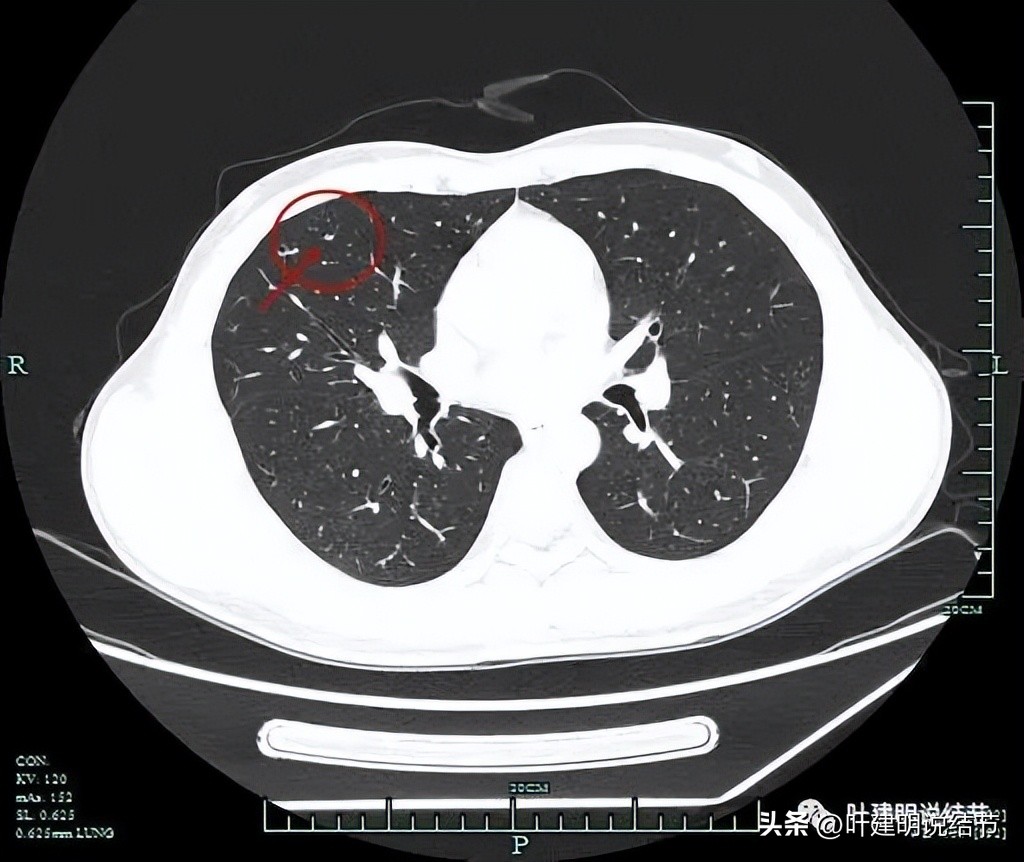

薄层平扫见三处病灶:

病灶3:右中叶内侧段胸膜下微小实性结节伴空泡征,密度过小,病灶过小,考虑良性结节。